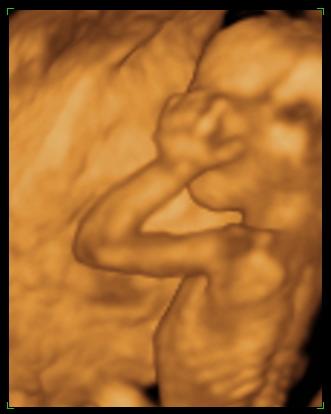

én még ilyen nehézkes nyaki redő mérést nem pipáltam... ok lementem gyalog a lépcsőn, ittam egy kávét, majd fel gyalog a negyedikig. Na ez meg is tette hatását- mikor visszahívtak, elkezdte mérni, megmérte vagy tízszer (!!!) a nyaki redőt. Nem mondott semmit. De én láttam alul a sarokban, hogy oda volt írva az NT, és hogy folyton ilyeneket mért, hogy 2,1,2,2,2,3....stb. mindig ekörül. Már törölgette a homlokát, összenéztek az asszisztenssel... kezdtem nagyon unni. Mondja egy idő után, hogy hát ő nem érti, de neki meg sem közelíti a 3-at.... mondja max 2.3-at mért idáig. Na mondom, az jobban hangzik, mint a 3.3. Akkor utána elkezdett a gyerek pörögni, kiegyenesedett, akkor is ilyeneket méregetett, majd a lepénytapadásra semmit nem mondott

, és mikor a gyerek kicsit hátrahajtotta a fejét, na akkor mért 2,8-3-at. És utána mondta, hogy ne haragudjak, de akkor ezt írja be, mert ha kicsit hátrahajtja a fejét, akkor vastagabb. De, szerinte nincs az 3 se, mindenesetre menjek el genetikai tanácsadásra....

Szoval tudjátok mit nem értek??? Nem az a normál állapot, ha nincs a feje hátrahajtva? Mikor pl. magasságot mérnek, akkor sem érvényes, ha hátrahajtom a fejemet,nem? Sőt ha a fejemet hátrahajtom, az én nyakam is vastagabb lesz, és megrövidül nem? Szerintetek másnak a nyaki redőjét is úgy mérik, hogy megvárják, míg hátrahajtja a fejét?!?!? Nem értem az egészet, komolyan... mindegy, a lényeg, hogy még így is kevesebbet mértek. szoval holnap megyek 11:30-ra a Bolgárkerékre a 4d uh-ra és a kombinált tesztre utána.